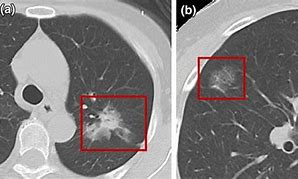

人类的肺脏是由一个个肺泡腔组成的,像一个个的小气球,血液通过肺泡壁与空气交换氧气和二氧化碳。当肺泡腔内存在液体渗出、炎性浸润、出血、新生物(如良性或恶性肿瘤)时,局部组织密度增高,肺泡含气量减少,就出现磨玻璃结节。